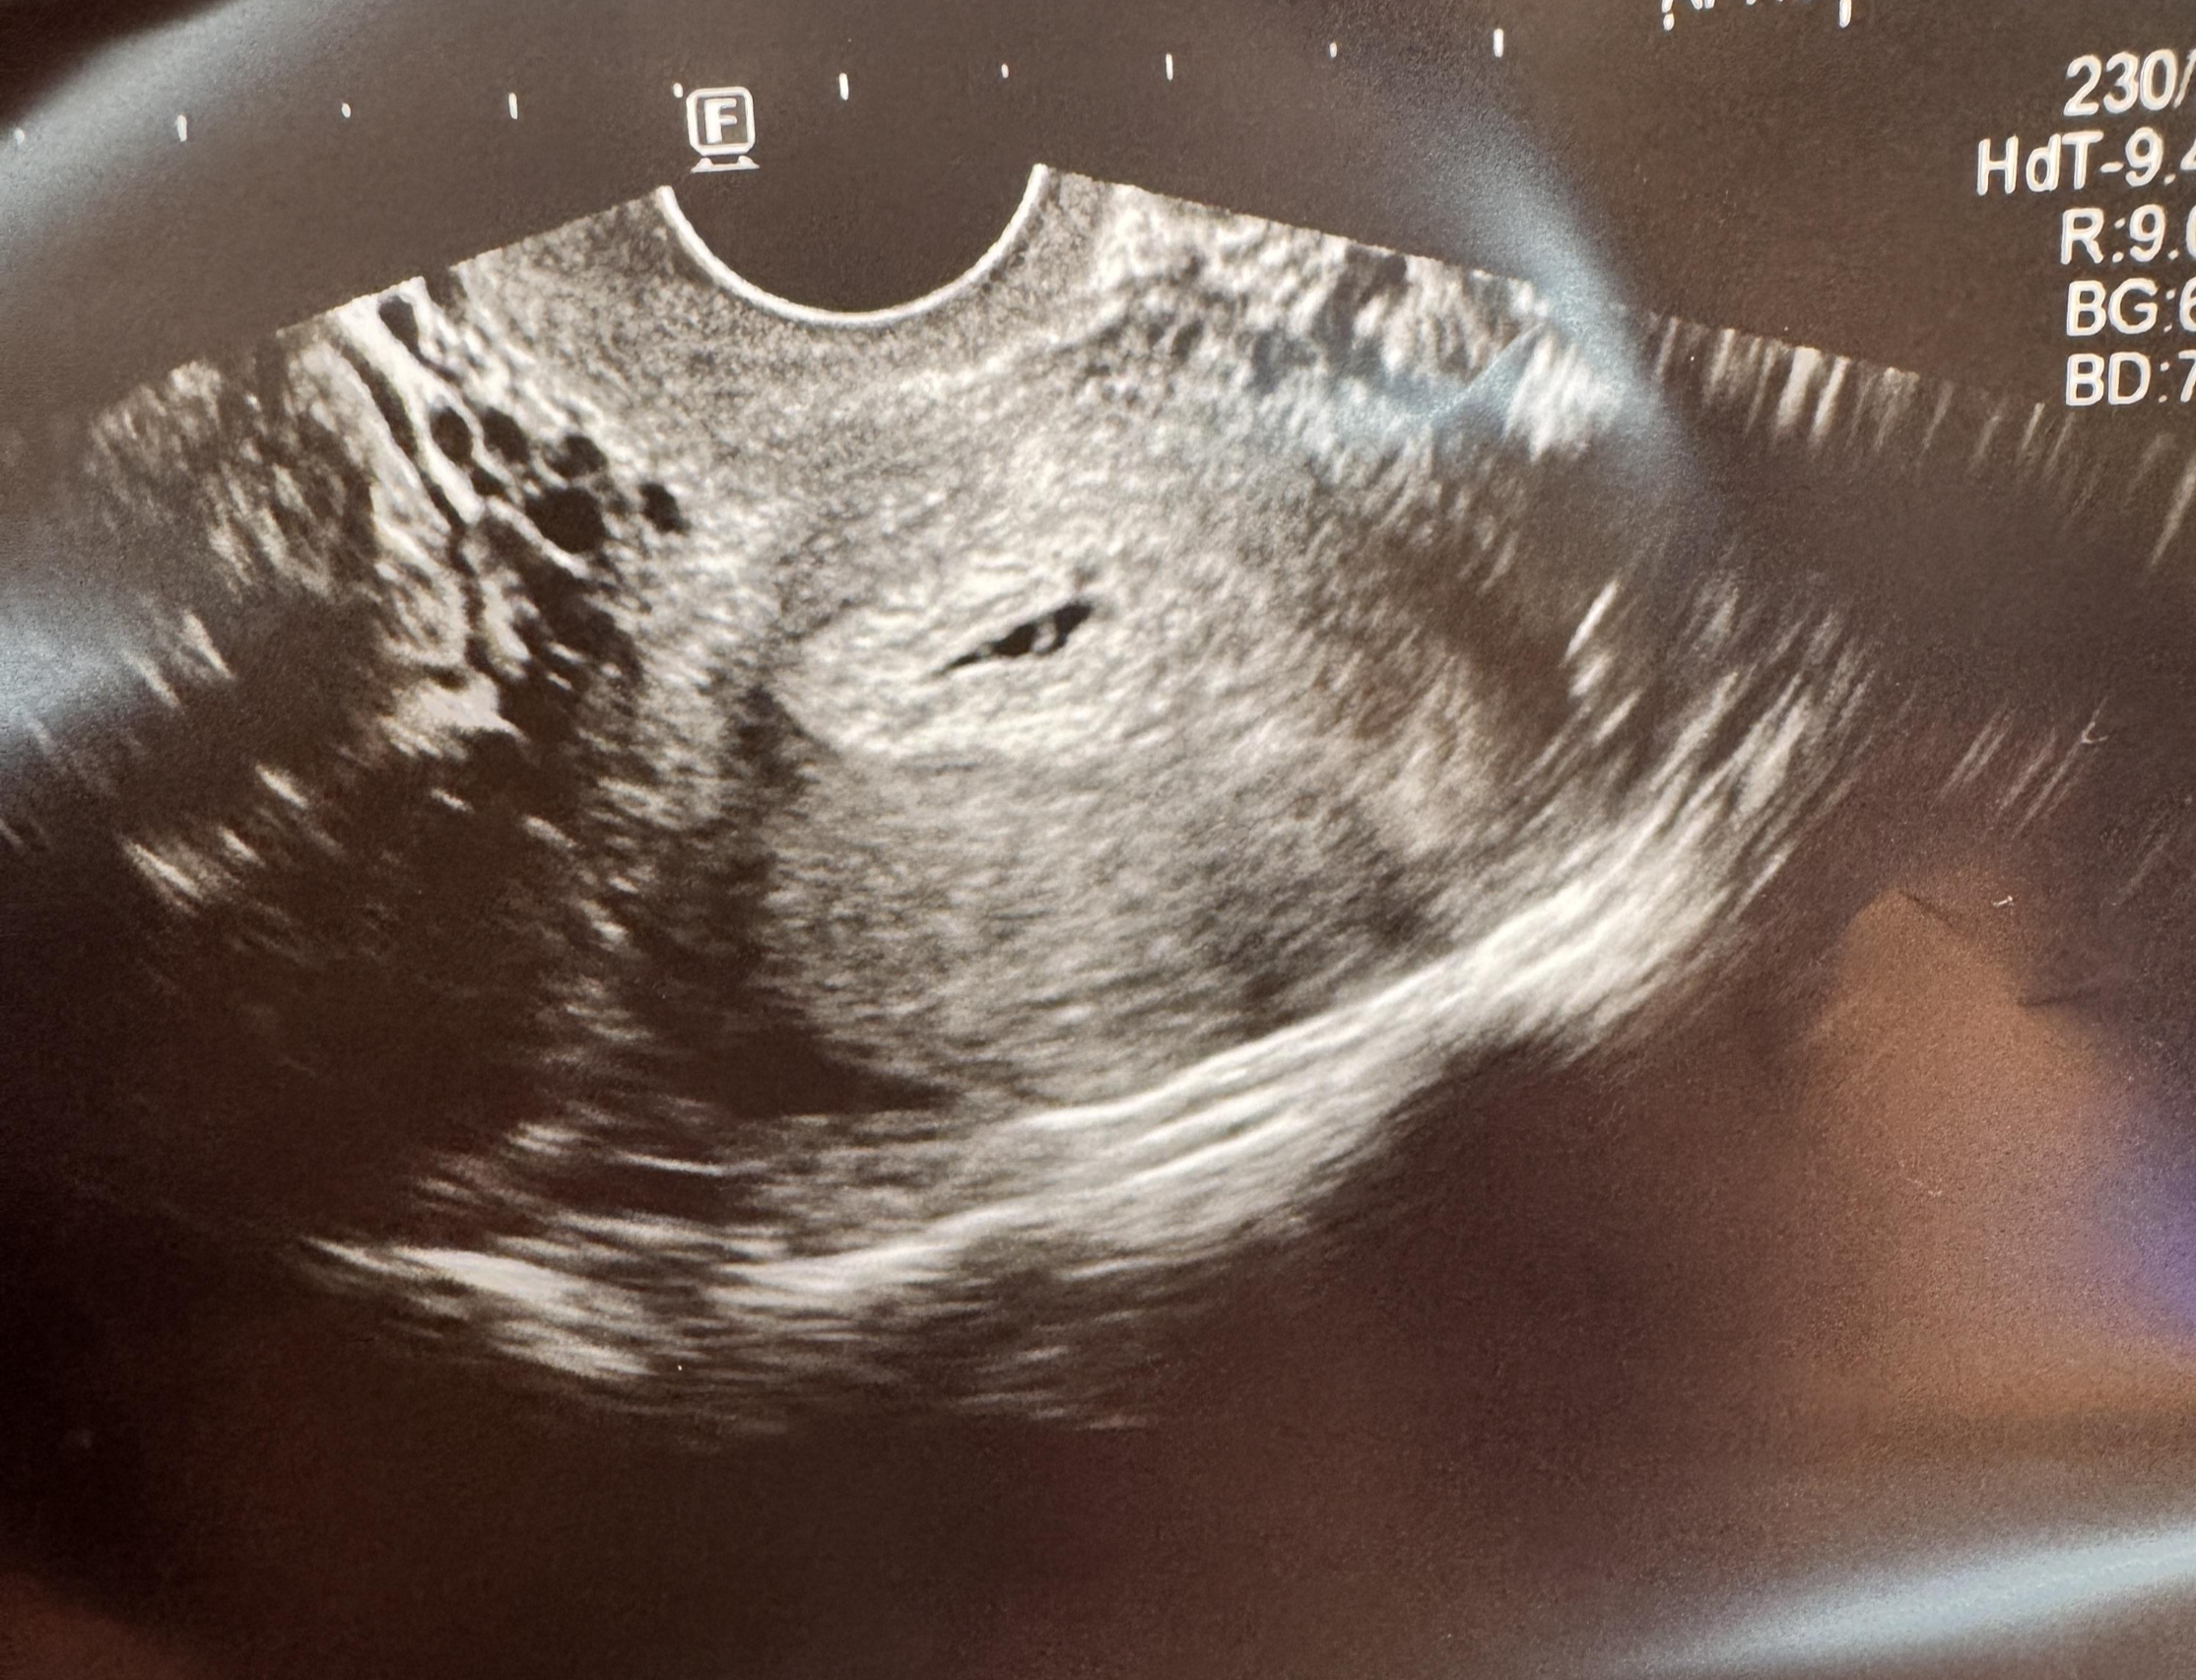

초보맘일지)_임신 5주 5일차 초음파_임신확인서 발급_임신 초기 주의 사항 본문

지난 포스팅 이후, 일주일이 지나고 드디어 5주 5일 차에 접어들면서 저도

아기집과 난황을 보고 왔는데요~!ㅎㅎ

저기 가운데에 보이는 검은색이 아기집이고

그 안에 동그랗게 자리 잡은 게 난황이라고 하더라고요~!

지난주에만 해도 흐릿해서 아기집도 형채만 보일 듯 말 듯 했던 것 같은데

그새 우리 아가가 이렇게 큰 거라고 생각하니 너무 기쁘더라고요ㅠㅠㅠㅠㅠㅠ